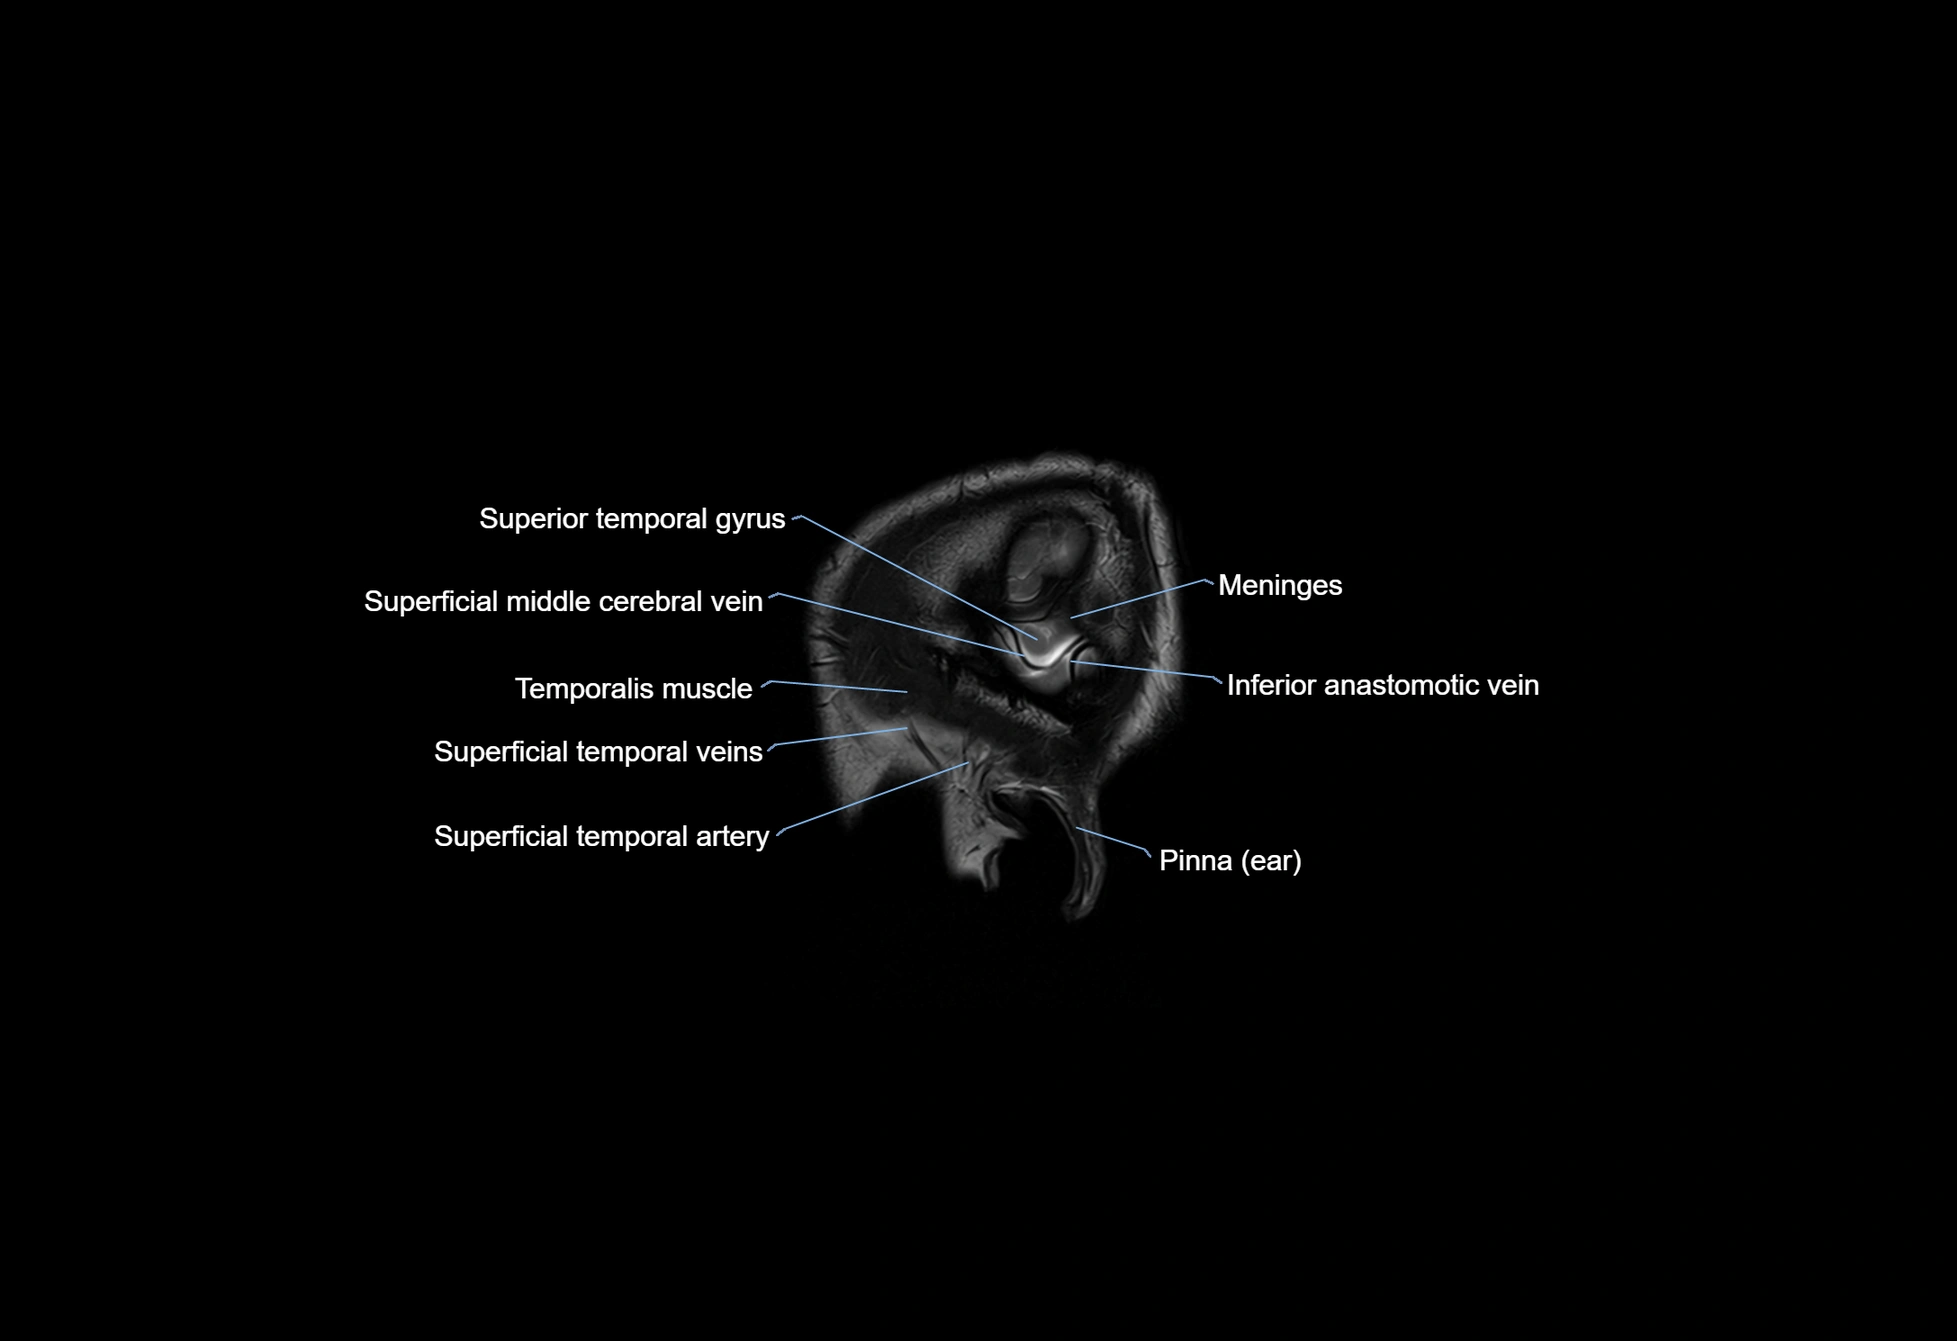

MRI images